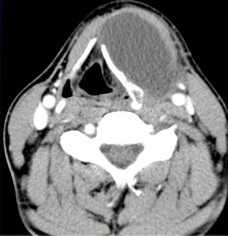

МРТ мягких тканей шеи. Т1-зависимая МРТ в аксиальной плоскости. Каротидная параганглиома справа.

Параганглиомы могут иметь несколько типичных локализаций (тимпаническая, вагусная, феохромоцитома и т.д.) в теле. На шее располагается каротидная параганглиома. Она представляет собой скопление хромафинных клеток в бифуркации общей сонной артерии, между наружной и внутренней. Некоторые из них активны, вырабатывают гормоны, повышающие артериальное давление. Часть опухолей имеет наследственное происхождение. Встречаются двухсторонние параганглиомы. Отличать от других опухолей помогает типичное место расположения, хорошее контрастирование при КТ и МРТ.